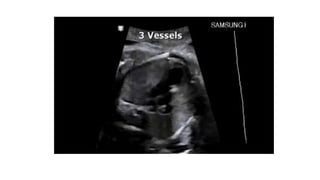

• #22 The three-vessel view. In this view, one can identify the three vessels from left to right (A) or anterior to posterior (B) as pulmonary artery (PA), aorta (A) and superior vena cava (V). The sizes of the pulmonary artery and aorta can be compared with the PA slightly larger than the aorta